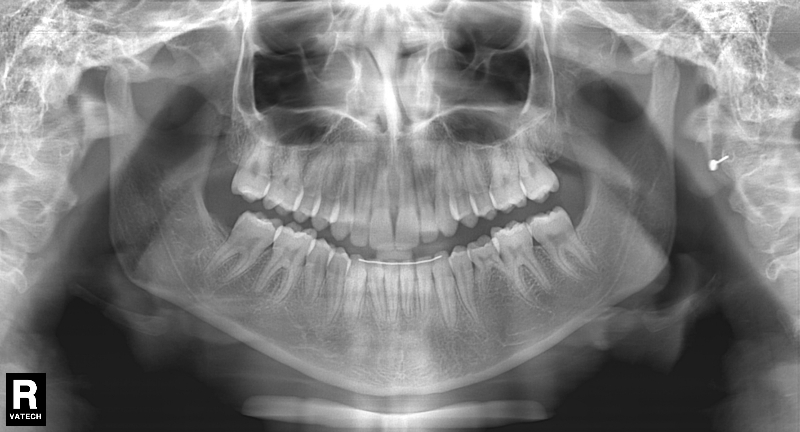

Premolar mandibular incluido + fenestración

45 incluido

Radiografía de final de tratamiento